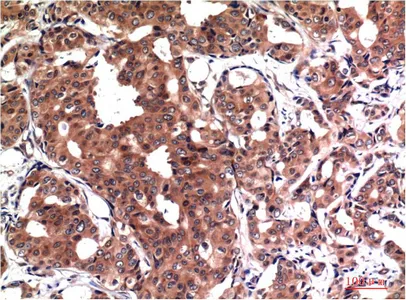

GSK3 beta (9F9) Mouse Monoclonal Antibody

Cat: AMM03603

GSK3 beta (9B1) Mouse Monoclonal Antibody

Cat: AMM03604

GSK3 beta (4C4) Mouse Monoclonal Antibody

Cat: AMM03605